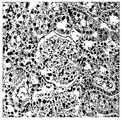

도 1은 다층 단계 구배 기술 (A- 좌측 패널) 또는 단층 혼합 구배 기술 (B-우측 패널)을 이용한 새로이 분해된 신장 조직으로부터의 epo-생성 세포 분획물의 농축을 나타낸다. 2가지 방법 모두에 의해 1.025 g/mL과 1.035 g/mL 사이에서 보이는 epo 밴드로부터 비 epo-생성 세포 성분 (주로 세뇨관 세포)이 부분적으로 고갈되었다.

도 35는 웨스턴 블롯을 통한 미세소포의 검출을 도시한다.Figure 1 shows the enrichment of epo-producing cell fractions from freshly digested kidney tissue using a multilayer step gradient technique (A-left panel) or a monolayer mixed gradient technique (B-right panel). Non-epo-producing cellular components (mainly tubular cells) were partially depleted from the epo bands seen between 1.025 g/mL and 1.035 g/mL by both methods.